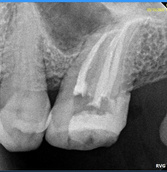

Es un procedimiento que

tiene como finalidad evitar la perdida del diente.

Para ello, se extrae la pulpa dental, se desinfecta y posteriormente se rellena y sella con material inerte y biocompatible.

¿Qué es una endodoncia?